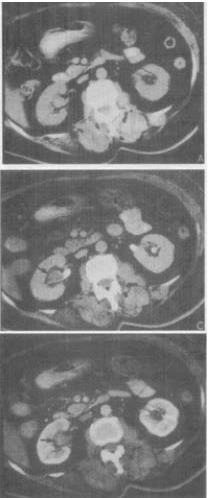

- 单项选择题 患者,女,53岁,右侧腰部不适1个月余,加重伴血尿10天。CT表现见图,最有可能是哪种疾病()。

A、肾癌

B、肾盂癌

C、错构瘤

D、肾腺瘤

E、肾结核

- B